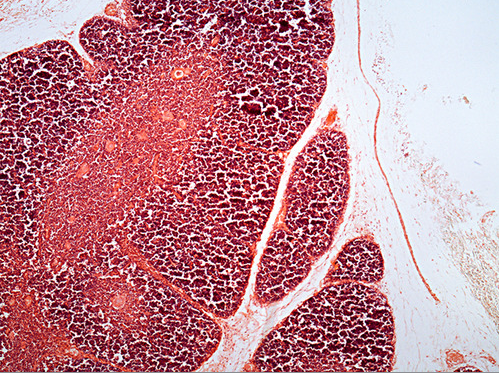

The organ indicated by the green arrow is the SPLEEN

The artery at the end of the green arrow is the central artery of the spleen.

The dark area marked by the green arrow is

white pulp in the spleen.

This is an image of which lymphatic organ? spleen